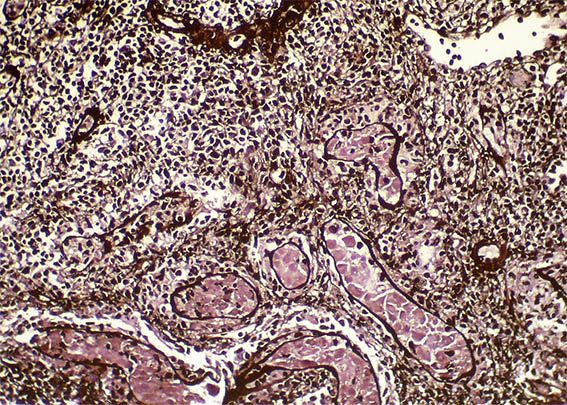

The patient is a 32-year-old man, kidney transplanted 18 months ago due to end-stage renal disease of unknown cause. A cellular rejection episode was evidenced in the first year. Good kidney function in the last control (16 post-transplantation months). Now in a new control the serum creatinine has risen to 1.9 mg/dL. Mild proteinuria and microscopic hematuria, no other abnormalities.

See the images of the renal allograft biopsy.

Figure 1. H&E, X100.